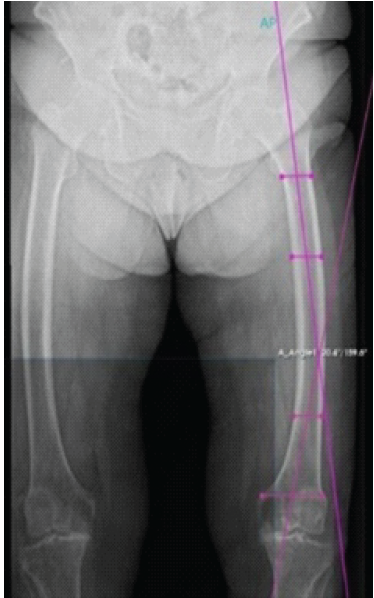

Femoral lateral bowing was defined as a coronal plane angle of ≥5°, according to Kim and Lee [5]. The lateral femoral bowing angle was measured using the Yau method, as described by Lee et al. [6], which has been shown to be highly reproducible (inter-rater reliability ≈ 0.98). Pre-operative measurements included a mechanical axis deviation of 16.2° of varus (Fig. 2), a lateral femoral bowing angle of 20.4 degrees (Fig. 3), lateral distal femoral angle of 95.2°, and medial proximal tibial angle of 89.2°.

Figure 3: Pre-operative radiographic measurement of femoral bowing angle of 20.4°.

Although no universally accepted classification system exists, according to Park et al. [7], this deformity corresponds to Grade III bowing, in which the reference line passes medial to the femoral cortex. Pre-operative digital templating and measurements were performed using PeekMed® software. This allowed precise quantification of deformity parameters, simulation of mechanical axis correction, and optimization of surgical strategies.